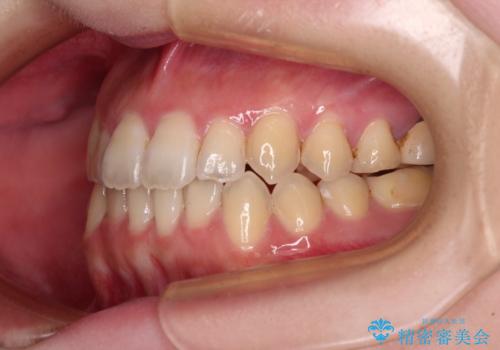

オープンバイトと前歯のデコボコをインビザライン矯正で解消

- 前歯の開咬を気にして来院された患者様です。

開咬の治療は、前歯を閉じるように動かすとともに、上下臼歯を圧下(骨内にめり込ませる)させることで進めて行きます。

インビザラインは臼歯の圧下を効果的に行えるため、インビザラインを用いて矯正治療を行うこととしました。